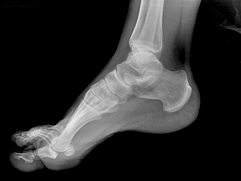

POSICION 2 : PIE L (LATERAL O PERFIL)

Paciente en decubito lateral, apoyando la cara lateral del pie sobre el cassete.El haz de rayos es dirigido verticalmente al centro del tarso.

CONSIDERACIONES MEDICAS Posicion 2 : PIE LATERAL

Enfoque complementario al frente de pie pero también importante en la apreciación de la patología talar y astragalina , no así el ante píe puesto que es mejor observado en el frente, , sin embargo es de uso común en la mesura de los arcos plantares ,

Los sesamoideos pueden ser observados en este enfoque en conjunción con un enfoque oblicuo , mucho de la patología plantar en lo que respecta a la fascia plantar y su inserción es mejor apreciada en este enfoque . Dr.Aramayo